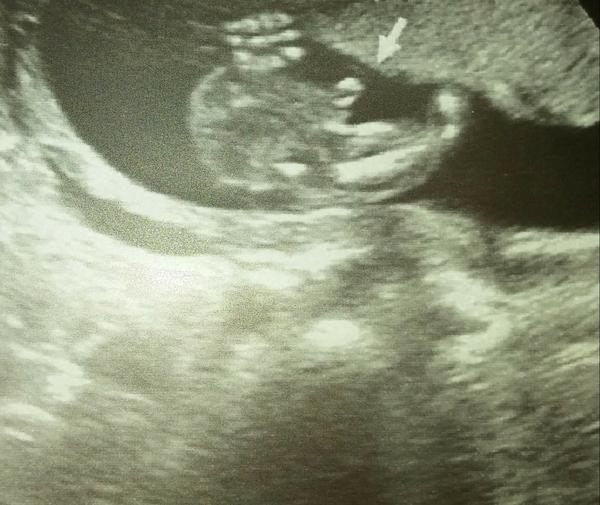

@micha.bello Dekuji moc za odpoved 🙂 Nemuze to byt pupecni snura? 🙂

Mam stejnou fotku .. a je to pinda 😃

@barbucha123 taky bych řekla, že to je chlapeček. Jako pupeční šňůra to moc nevypadá a já jsem měla na utz u obou holčiček jasné kávové zrno a to vypadalo jinak 🙂 Ale můžu se mýlit.